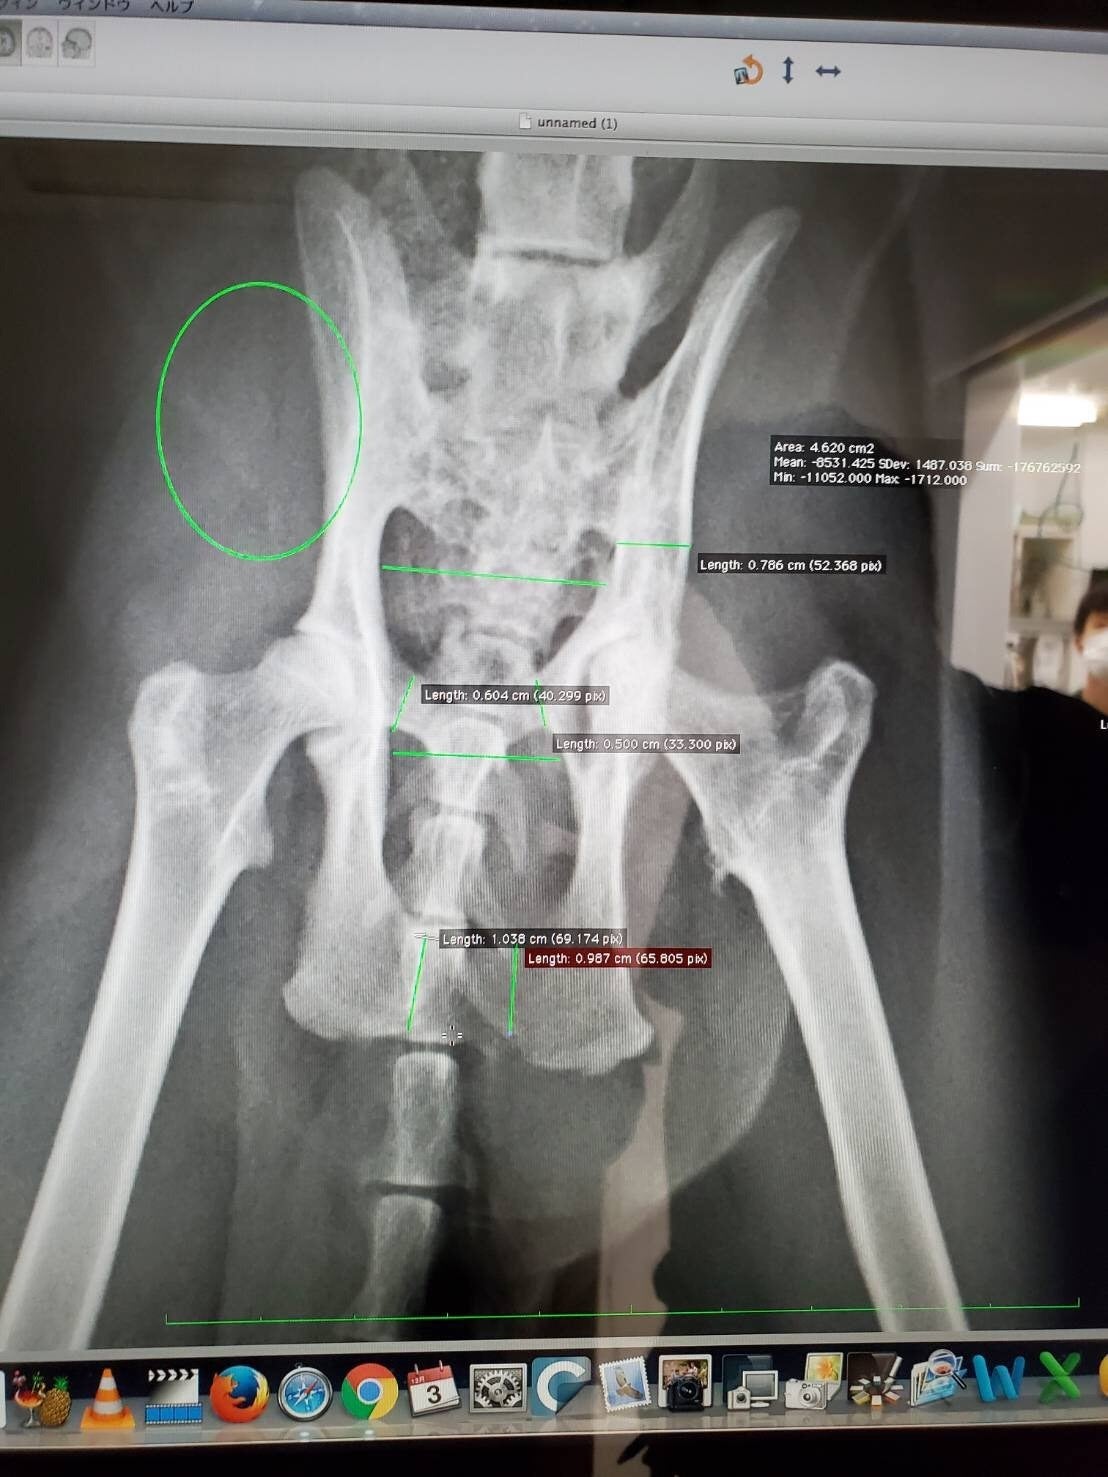

子猫で保護した時に骨盤骨折をしていて

便が出にくくなる巨大結腸症になっている めるちゃん3歳男の子です。

やはり手術をしないといずれ便が出なくなるとの診断。

骨盤を正常位置に戻す手術で難しい手術になりそうです。